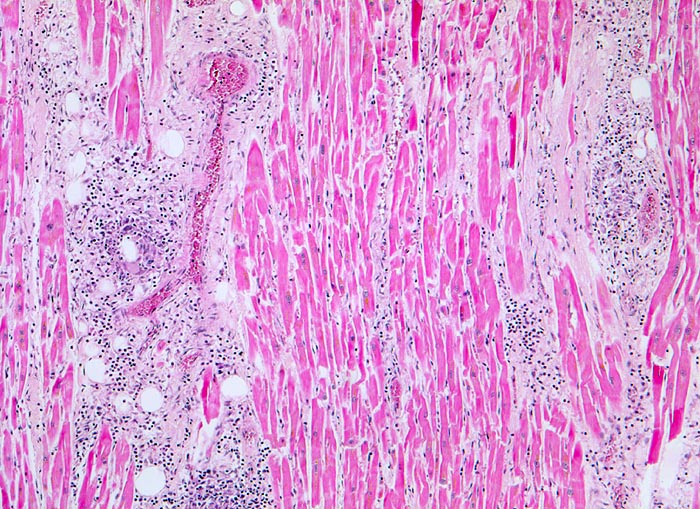

Bei etwa 30 bis 50% der Patienten mit vermuteter Myokarditis lassen sich bioptisch Veränderungen nachweisen. Wegen der herdförmigen Verteilung der Entzündung können beim Biopsieren Trefferfehler auftreten. Histopathologisch lassen sich in der ersten Biopsie eine akute (=aktive) und eine chronische Myokarditis unterscheiden. Bei beiden findet sich ein diffuses, fokales oder konfluierendes Entzündungsinfiltrat quantifiziert durch Immunhistochemie (>14 Lymphozyten und Makrophagen/mm2) und eine Fibrose. Bei der aktiven Myokarditis sind zusätzlich obligat Nekrosen oder eine Degeneration von Herzmuskelzellen nachweisbar.

• Teils fleckförmiges, teils diffuses gemischtes Entzündungsinfiltrat aus Lymphozyten, Plasmazellen, Makrophagen und zahlreichen eosinophilen Granulozyten.

• Einzelne Herzmuskelzellen werden durch das Entzündungsinfiltrat zerstört und sind hypereosinophil (Myozytolyse).

• Interstitielles Ödem (Auflockerung des Gewebes).

• Fleckförmige Fibrose.